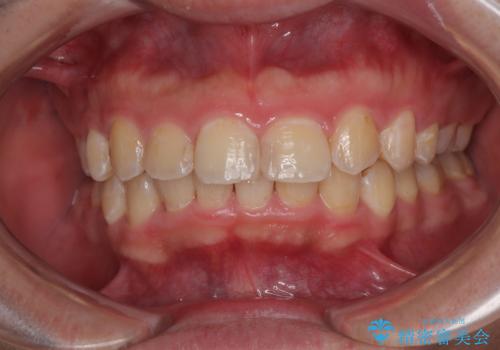

咬合平面を平坦にしながら前歯の咬み合わせを挙上し、デコボコと鋏状咬合も改善していくこととしました。

骨格的な左右差が大きかったため、上下の正中のズレや、左右奥歯の咬み合わせなどは妥協的な仕上がりとなりました。

骨格的なズレに対応するにはワイヤー矯正が至適であり、マウスピース矯正は選択しないようにお話をしました。